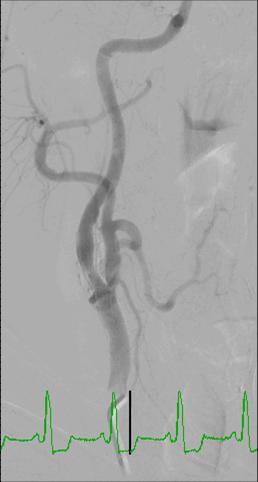

Angiography for the diagnosis of carotid artery stenosis

Angiography is the traditional ‘gold standard’ for the imaging of blood vessels. Direct angiography offers the best means for visualization of carotid artery lesions and overcomes most of the limitations that were listed for the other methods. The main disadvantages of carotid artery angiography include:

- It is an invasive procedure

- It exposes patients to ionizing radiation and contrast material

Therefore, nowadays angiography is utilized only when the non-invasive methods gave inconclusive results.